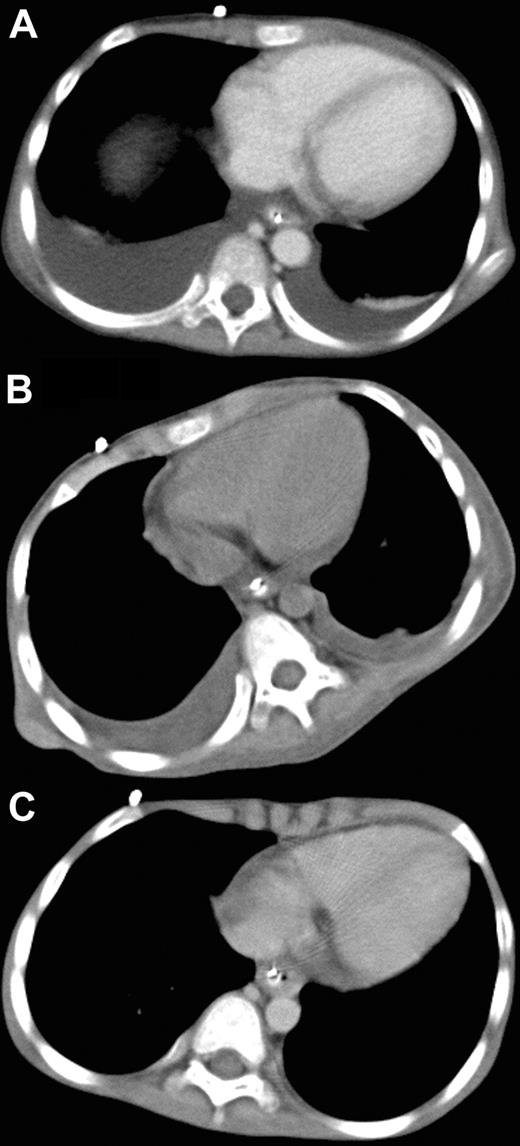

A 6-year-old male with Fanconi anemia received marrow cells from a HLA–DRB1 mismatched unrelated donor as previously described.4 On day 22 after SCT, the patient developed posterior reversible encephalopathy syndrome with mild systemic edema, suggesting generalized injury of the vascular endothelium. Subsequently, grade 2 acute graft-versus-host disease of the skin and gastrointestinal tract ensued but was easily controlled with prednisolone. However, systemic edema accompanying consciousness disturbance, tachypnea and tachycardia developed 68 days after SCT. Computed tomography (CT) revealed massive pleural effusion (Figure 1A) and ascites, and the patient was diagnosed with CLS. Despite intensive conventional treatments, including prednisolone (1 mg/kg daily), ulinastatin (10 000 units/kg daily), and albumin (0.8 g/kg every other day), hypotension, negative central venous pressure, and anuria developed 72 days after SCT. Because of the patient's critical condition and lack of response to other therapies, his case was discussed in the transplantation peer review group. Off-label use of bevacizumab was recommended. Written informed consent to the treatment in accordance with the Declaration of Helsinki and permission to publish results were obtained from the parents separately before the study and after the study, respectively. The publication of this study involving bevacizumab administration was approved by the institutional review board of Tokai University Hospital. Rationale and potential side effects were also discussed with the parents. Intravenous bevacizumab (5 mg/kg body weight) was administered over a 90-minute period. On the first day after treatment, urine production started to improve, and blood pressure and central venous pressure returned to the normal range. On the second day, all symptoms were ameliorated. A marked decrease in the amounts of pleural effusion was evident on the CT films obtained on the fifth day after bevacizumab administration (Figure 1B), and complete resolution of pleural effusion was revealed on the CT films taken 20 days after the treatment (Figure 1C). Plasma VEGF level before bevacizumab administration was not elevated (27 pg/mL; normal, < 115 pg/mL).

Administration of bevacizumab. Chest CT before (A), 5 days after (B), and 20 days after (C) treatment with bevacizumab.